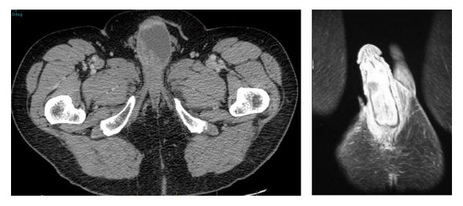

• Ультразвуковое исследование полового члена, тазовых и абдоминальных органов, лимфатических узлов. Сонография позволяет определить глубину прорастания неоплазии и наличие отдаленных метастазов.

• МРТ – высокоинформативное исследование, предоставляющее исчерпывающую информацию о стадии развития процесса.